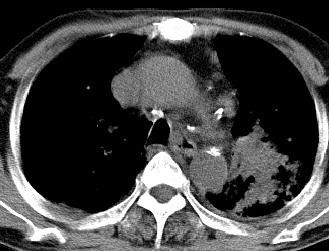

以下是引用xianxianzhongyi在2008-4-20 14:44:00的发言:[br]本人愚见:次病例短短两月的时间,呈现如此大面积实变,病变增长过于迅速,此其一。其二,病变在动脉早期既有明显强化。其三,左上叶后段及下叶背段多叶受累。其四,肺门及纵隔内未见明显肿大的淋巴结。估计层面较厚段支气管显示不清。 诊断:炎性实变可能性大。

以下是引用光影相伴在2008-4-20 14:39:00的发言:[br]支持:1)左侧中央型肺癌伴左肺上叶阻塞性肺炎。、[br] 2)双侧少量胸腔积液。